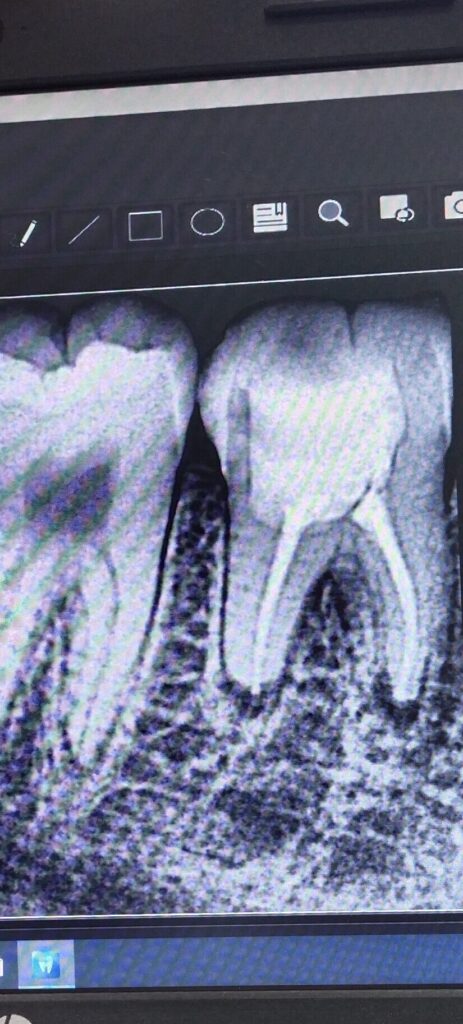

In the second visit, the canals were obturated, and the tooth was filled with composite material to restore its function and appearance. The patient tolerated the procedure well, with no pain reported during the visit.

Outcome: Radiographs taken before, during, and after the root canal treatment revealed that the tooth was properly cleaned, shaped, and obturated, ensuring the success of the treatment.